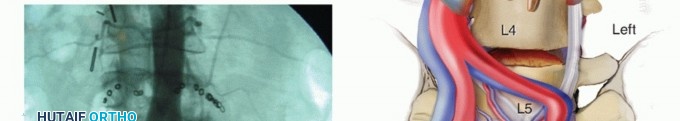

At L5-S1, retract the left common iliac artery and vein to the patient's left and the right common iliac artery and vein to the right. At levels above L5-S1, the aorta and inferior vena cava must be mobilized to the patient's right.

The great vessels can be held in their retracted position using handheld Hohmann retractors, custom-designed pins, or Kwires, all of which can be advanced directly into the vertebral bodies (virtually eliminating the risk of vessel migration into the field of interest) (TECH FIG 1B).

Alternatively, stainless steel vein retractors or radiolucent retractors can be fixed to the arms of an abdominal retractor system (Omni) or floating, Endo ring-type retractor system. These blade retractors have the disadvantage of allowing vessel migration into the field by sliding under the retractor blades as motion occurs during the procedure. The advantage of the radiolucent retractors is that better visualization of the operative field is possible with fluoroscopy. In addition, blade-type retractors can be

easily manipulated during the procedure without having to reinsert into the vertebral body.